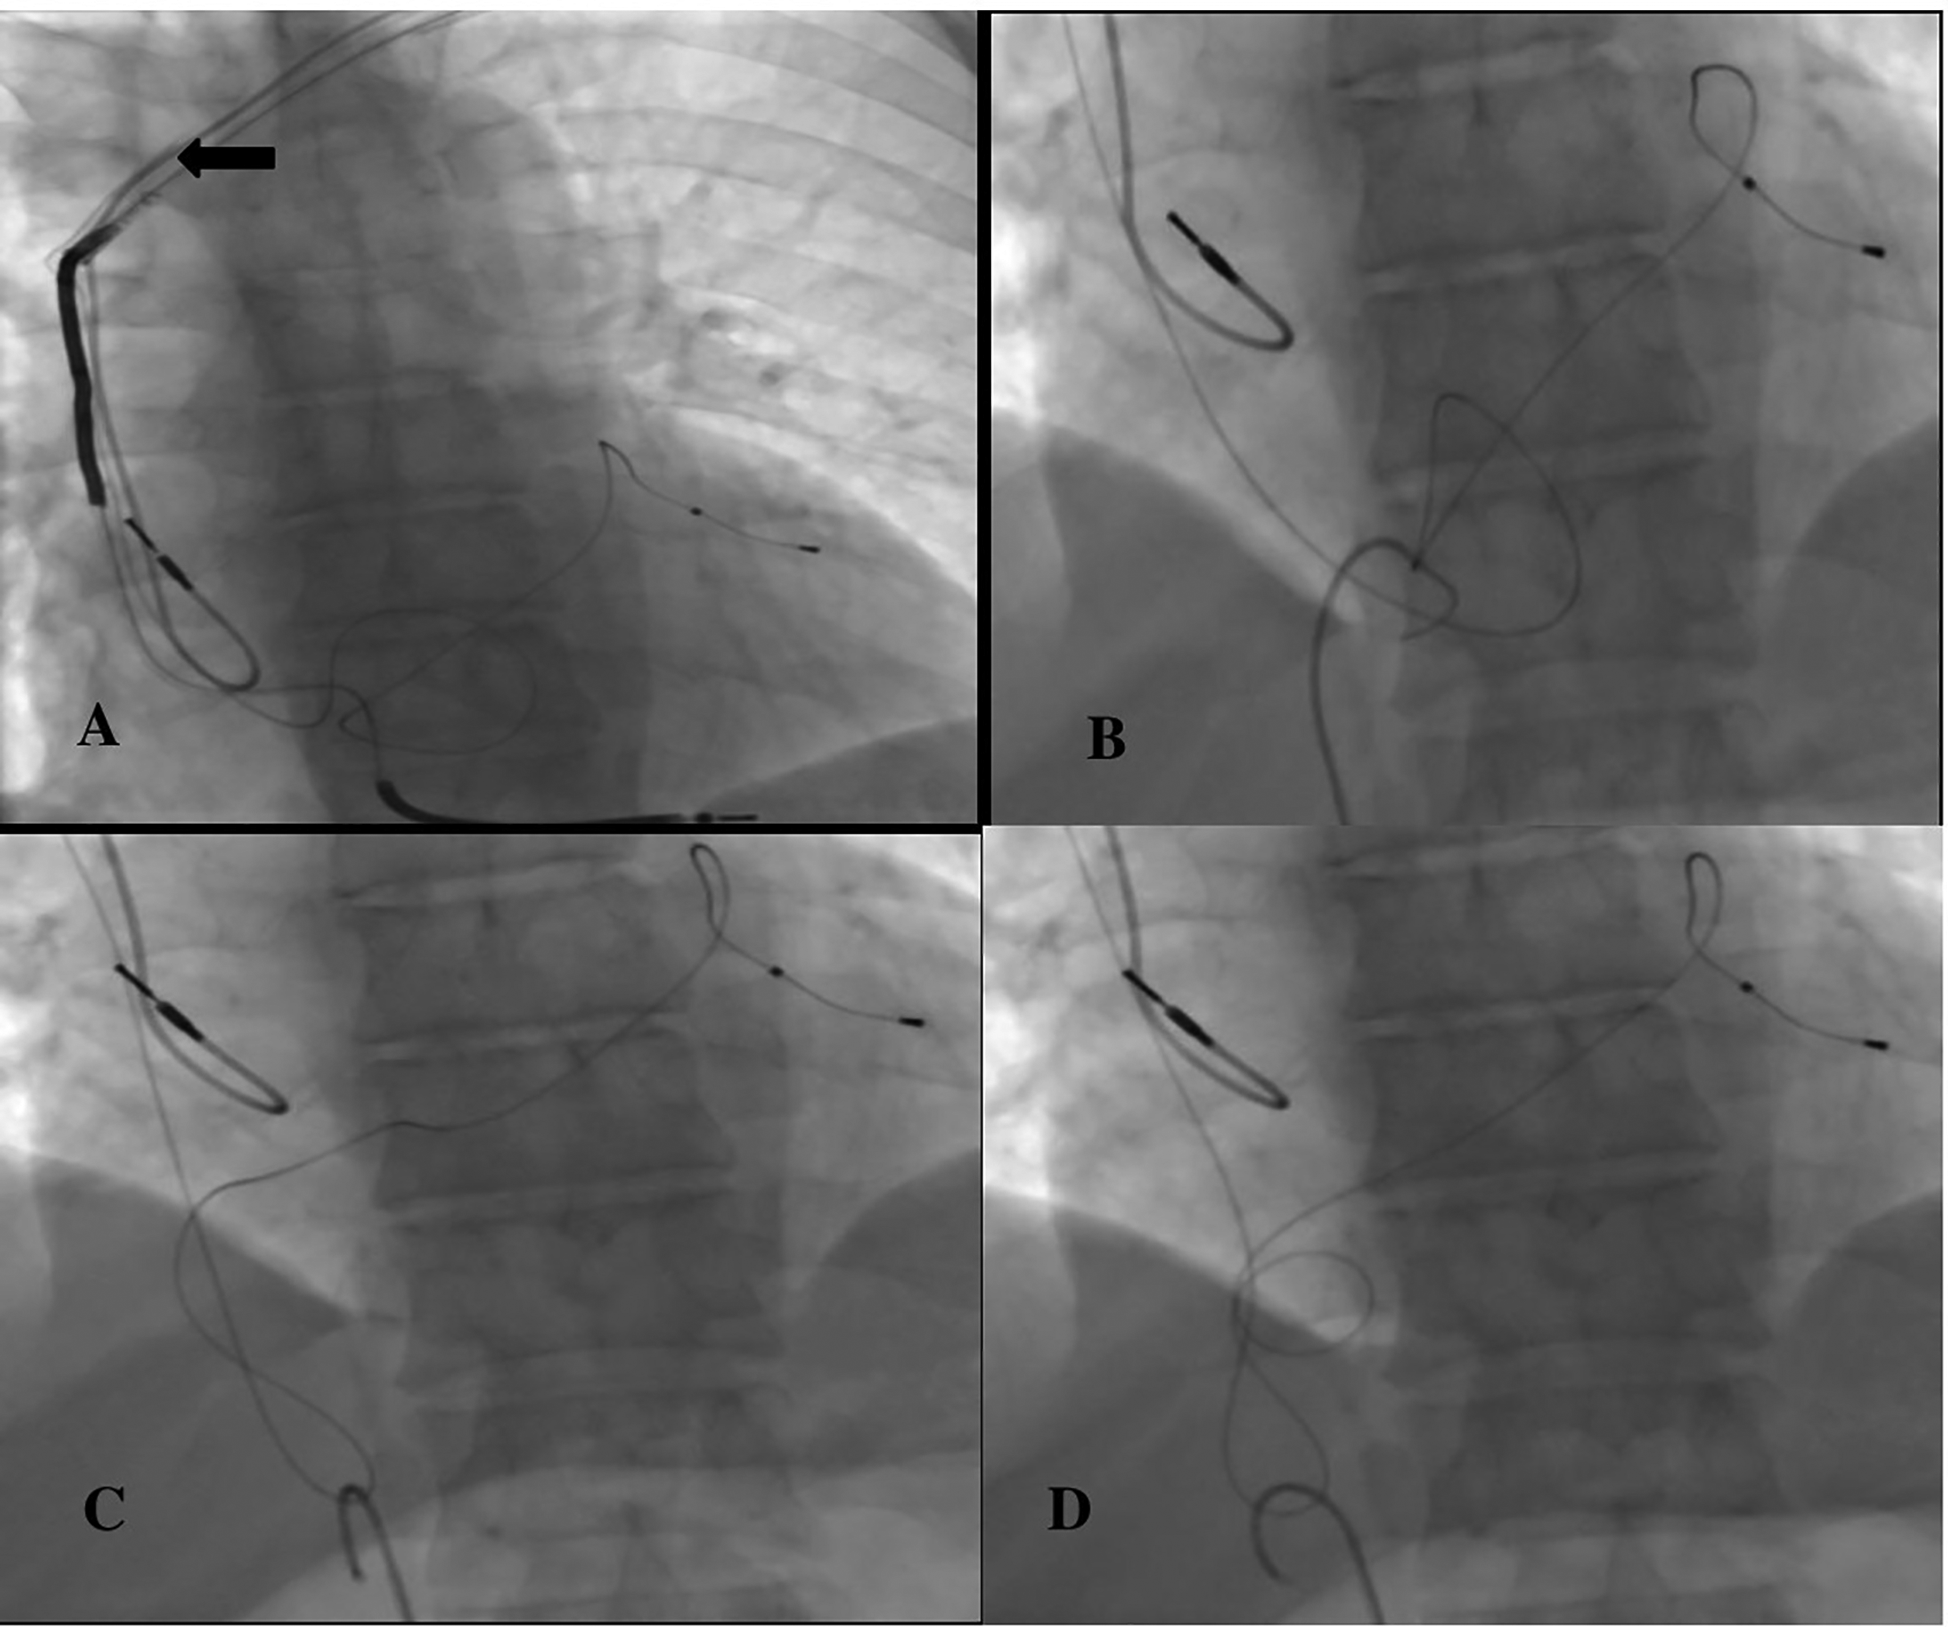

The patient was taken to the cath laboratory, and an incision was made at the pace site, and the leads were accessed. The transvenous lead extraction device (TLED) was advanced towards the superior vena cava, incorporating the right ventricular lead. Meanwhile, there was difficulty in moving the device forward. Subsequently, the coronary sinus (CS) lead broke off. (Figure 2A). The process continued. First, the right ventricular lead was removed. Then, the 9F sheath was entered through the right femoral vein. A 6F pigtail catheter was sent from the sheath. An attempt was made to capture the CS lead with the catheter. The tip of the catheter caught the lead, (Figure 2B) it was turned clockwise and wrapped around the catheter in a spiral shape (Figure 2C). By applying a downward pulling force, it was seen that the CS lead was coming (Figure 2D). The lead was withdrawn up to the femoral sheath (Figure 3A). After withdrawing up to the femoral sheath, it was observed that the lead was stripped from the catheter again at the entrance of the sheath. The lead was captured and removed by sending a snare through the sheath (Figure 3B). No effusion was observed on echocardiography. The procedure was terminated by reinserting the ventricle and coronary sinus lead (Figures 3C,D). The procedure took approximately 25 min from the breakage of the Cs lead until it was removed with a pigtail. During this process, 300 gray of radiation was exposed. After the patient was monitored in the coronary intensive care unit for 1 day, he was transferred to the ward and discharged. No complications or problems were observed during the 1st and 3rd month follow-up.

Figure 2

(A) ← Broken CS lead, (B) capturing the CS lead with a pigtail catheter, (C,D) turning the pigtail catheter clockwise and wrapping it around the lead.